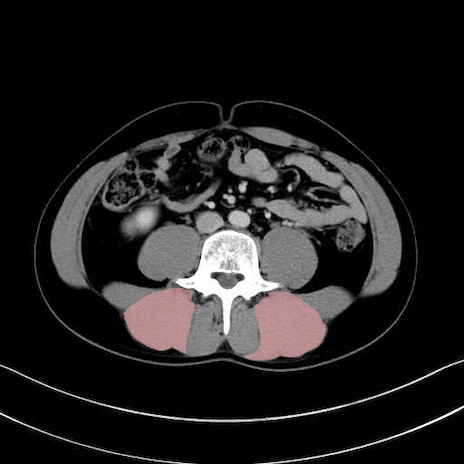

脊柱起立筋 (Erector spinae)

多裂筋 (Multifidus)